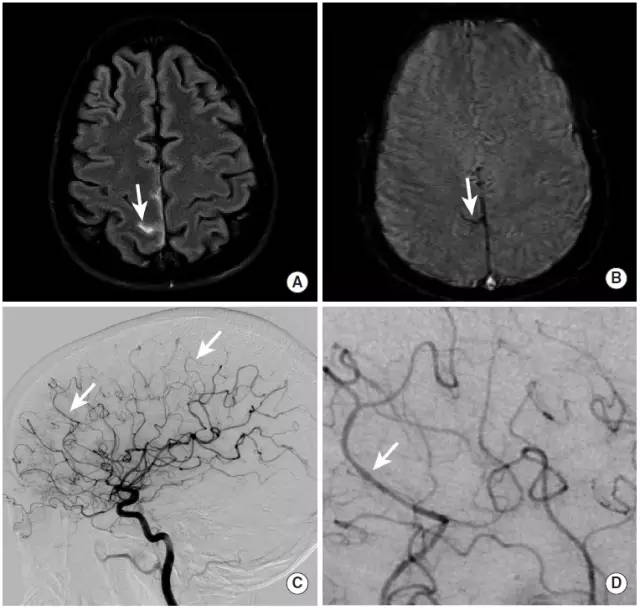

图16

中年女性,主要症状为头痛,后证实为继发于脑动脉血管炎的蛛网膜下腔出血。

图A:MRI的FLAIR成像可见右缘沟内的异常高信号(长尾箭头)。

图B:GRE序列进一步证实了脑沟内异常低信号,为蛛网膜下腔出血(长尾箭头)。

图C、D: DSA显示右侧大脑中动脉M4段(长尾箭头)和右侧大脑前动脉远端(未示出)微小的串珠样改变,与血管炎表现一致。